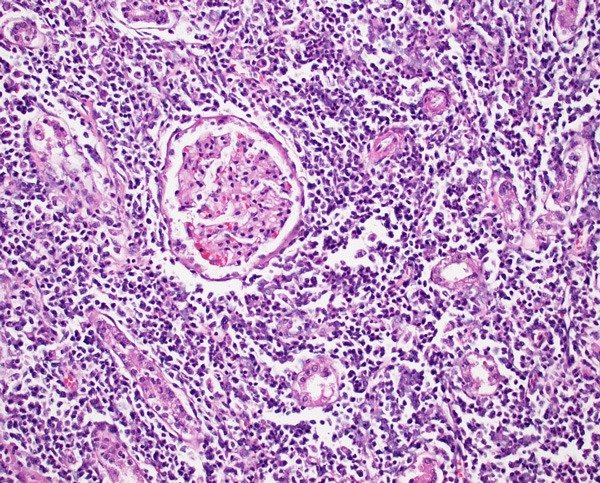

Photomicrograph of canine kidney with leptospirosis. Numerous leukocytes infiltrate the interstitium, separating and sometimes effacing renal tubules. This pattern is compatible with tubulointerstitial nephritis. An intact glomerulus is identified at the center of the image.